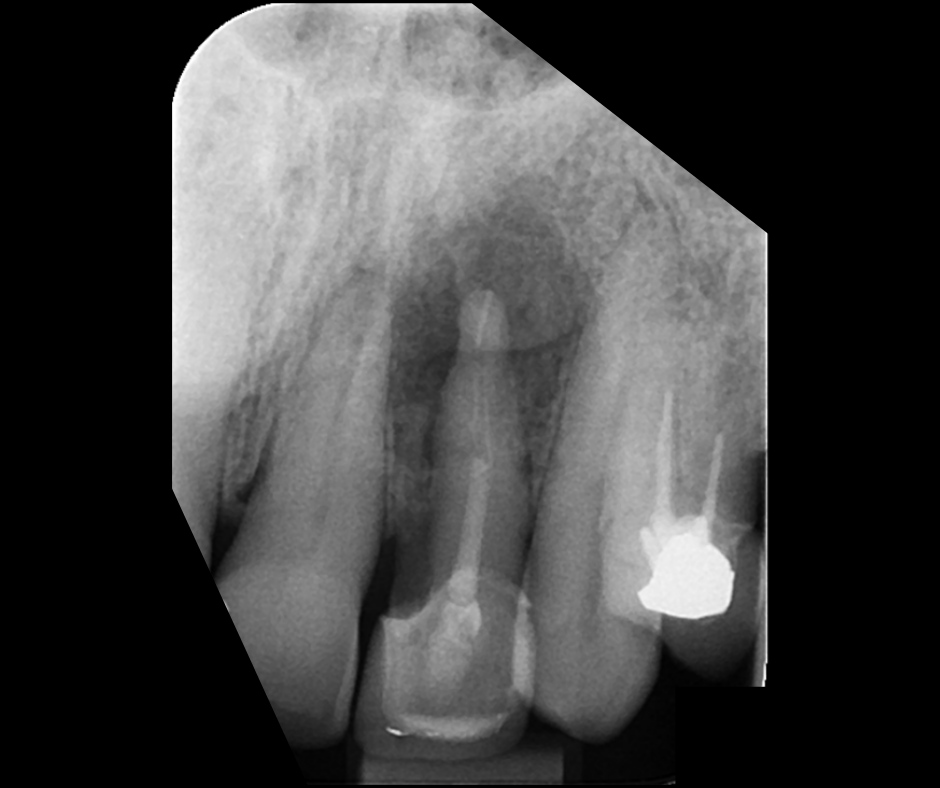

This course focuses on modern single-file endodontic systems, guiding participants through diagnosis, case assessment, access cavity design, canal location, root canal system preparation, and obturation techniques.

• To re-examine access cavity design and its importance in endodontic success

• To understand the importance of achieving patency and mechanical glidepath with hand & NiTi instruments

• To gain confidence in mechanical preparation using rotary and reciprocating NiTi shaping instruments

• To gain confidence in endodontic obturation and develop an understanding of various obturation techniques and methods of developing predictable, reproducible endodontic obturation